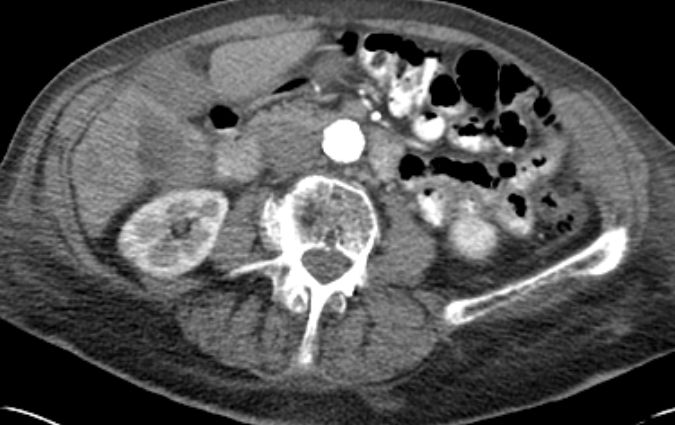

86-jähriger Mann, bei dem vor 9 Monaten eine Cholezystektomie wegen gedeckt perforierter Cholezystitis vorgenommen wurde. Jetzt Verdacht auf Leberabszess. Die laparoskopische Biopsie ergab ein Adenokarzinom. Die Nachbefundung der Gallenblase erbrachte immunhistochemisch den Nachweis eines Gallenblasenkarzinoms. | ||